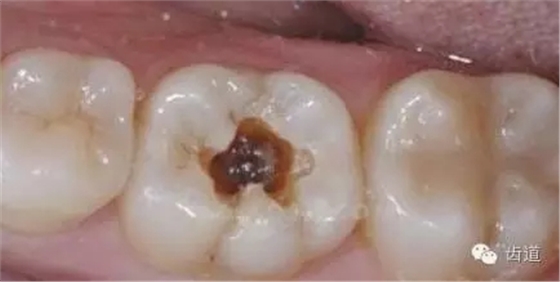

1、患淺齲、中齲的乳前牙,齲壞面廣泛或釉質(zhì)發(fā)育不全并發(fā)廣泛齲壞而不易備洞的后牙。行磨除法配合氟化鈉甘油涂擦。有條件時可再用專用漱口劑,如口潔素、口腔寶等。

2、淺齲:充填術(shù)。

3、中齲:墊底充填或直接充填。

4、深齲:如洞底變色軟齲去凈且牙髓狀況正常,行OC安撫術(shù)、間接蓋髓、墊底充填。如軟齲不能去凈或牙髓充血,行根管治療術(shù)+全冠修復(fù)